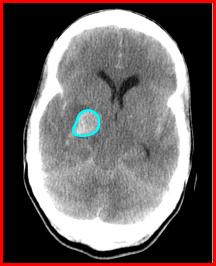

A complication of old cerebral infarcts is that they can rebleed as is the case here. The edema associated with large infarcts can compress local small blood vessels. As the edema subsides, reperfusion of the damaged vessels can lead to hemorrhage.

Here is another patient who had a thrombotic infarct 2 weeks prior to this CT and now presents with new cognitive deficits.

What do you think happened?

The degree of effacement here is consistent with an infarct that occurred at least a few days prior.